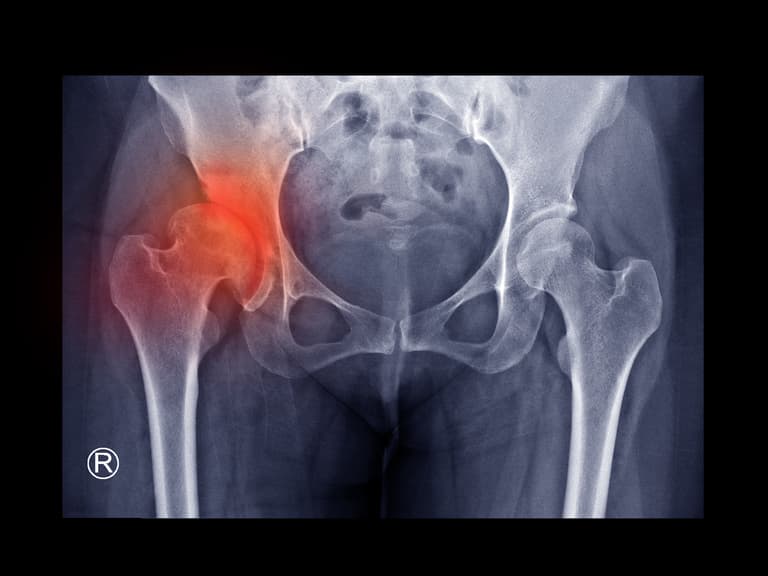

Hip Impingement Syndrome

PD Dr. med. Patrick Weber is a highly respected specialist in the implantation and revision of hip and knee endoprostheses. With extensive academic and surgical experience, he is recognized as one of Germany’s leading experts in modern joint replacement surgery. During his many years at the University Hospital of Munich (LMU) – Klinikum Großhadern, Dr. Weber served as Head of Hip Arthroplasty and Deputy Head of Knee Arthroplasty, gaining comprehensive expertise across the full spectrum of endoprosthetic surgery—including highly complex cases such as hip dysplasia and post-traumatic osteoarthritis. Expertise in Minimally Invasive Hip Replacement (AMIS) For many years, Dr. Weber has specialized in the minimally invasive, muscle-sparing implantation of hip prostheses using the AMIS method. He is internationally regarded as a reference surgeon and instructor for this advanced technique, which supports faster recovery and improved mobility. Another major focus of his work is the revision and replacement of existing hip and knee implants, particularly in cases of loosening, pain, or implant failure. Key Areas of Specialization Dr. Weber’s surgical expertise includes: Hip replacement surgery using the AMIS approach Knee replacement surgery, including unicondylar (partial) knee prostheses Implantation of hip and knee prostheses in complex anatomical situations, such as: Hip dysplasia Post-traumatic arthritis Revision arthroplasty (exchange of hip and knee prostheses) Conditions Treated Dr. Weber provides expert care for patients with: Coxarthrosis (hip osteoarthritis) Gonarthrosis (knee osteoarthritis) Painful or loosened endoprostheses Femoral head necrosis (avascular necrosis) Academic & International Recognition With more than 150 scientific publications and international lectures, PD Dr. Weber is a regularly invited speaker at leading national and global congresses focused on joint replacement and endoprosthetics. His combination of surgical precision, minimally invasive expertise, and academic leadership makes him a trusted authority in advanced hip and knee arthroplasty.

Director of the Hip Center – ATOS Clinic Munich The Hip Center at ATOS Clinic Munich is led by Dr. med. Raimund Völker, a founding member of the clinic and one of the most experienced specialists in hip endoprosthetics worldwide. Dr. Völker is among the very few internationally recognized surgeons who exclusively dedicate their practice to hip surgery. This exceptional level of specialization provides significant advantages for patients, allowing for highly precise treatment planning, advanced surgical expertise, and consistently outstanding outcomes. With over 20 years of experience in both standard hip replacement and bone-preserving hip resurfacing, Dr. Völker offers each patient the most suitable procedure based on individual anatomy, lifestyle, and long-term goals. Excellence in Hip Arthroplasty & Implant Quality Unlike standard approaches that rely on routine implants, Dr. Völker uses only high-quality, long-established original prosthetic systems at ATOS Clinic. This ensures: Maximum implant durability Long-term safety Excellent functional results His philosophy combines proven methods with innovation to provide the best possible joint replacement strategy for every patient. Minimally Invasive & Muscle-Sparing Surgery Dr. Völker applies modern surgical techniques that are: Minimally invasive Muscle-sparing Bone-conserving These approaches support faster recovery, improved mobility, and enhanced joint stability. Together with individualized implant selection and early intensive physiotherapy, patients benefit from an optimized Fast Track Recovery program. Key Areas of Expertise & Procedures Dr. Völker’s clinical focus includes: Diagnosis and treatment of hip osteoarthritis and its causes Advanced cartilage treatment options, including MRI-based cartilage cell therapy Total hip replacement (total endoprosthesis) Hip resurfacing surgery following the McMinn method (BHR) Short-stem hip prostheses Minimally invasive hip replacement techniques Enhanced Recovery Programs (ERP) Computer-assisted navigation for surgical precision